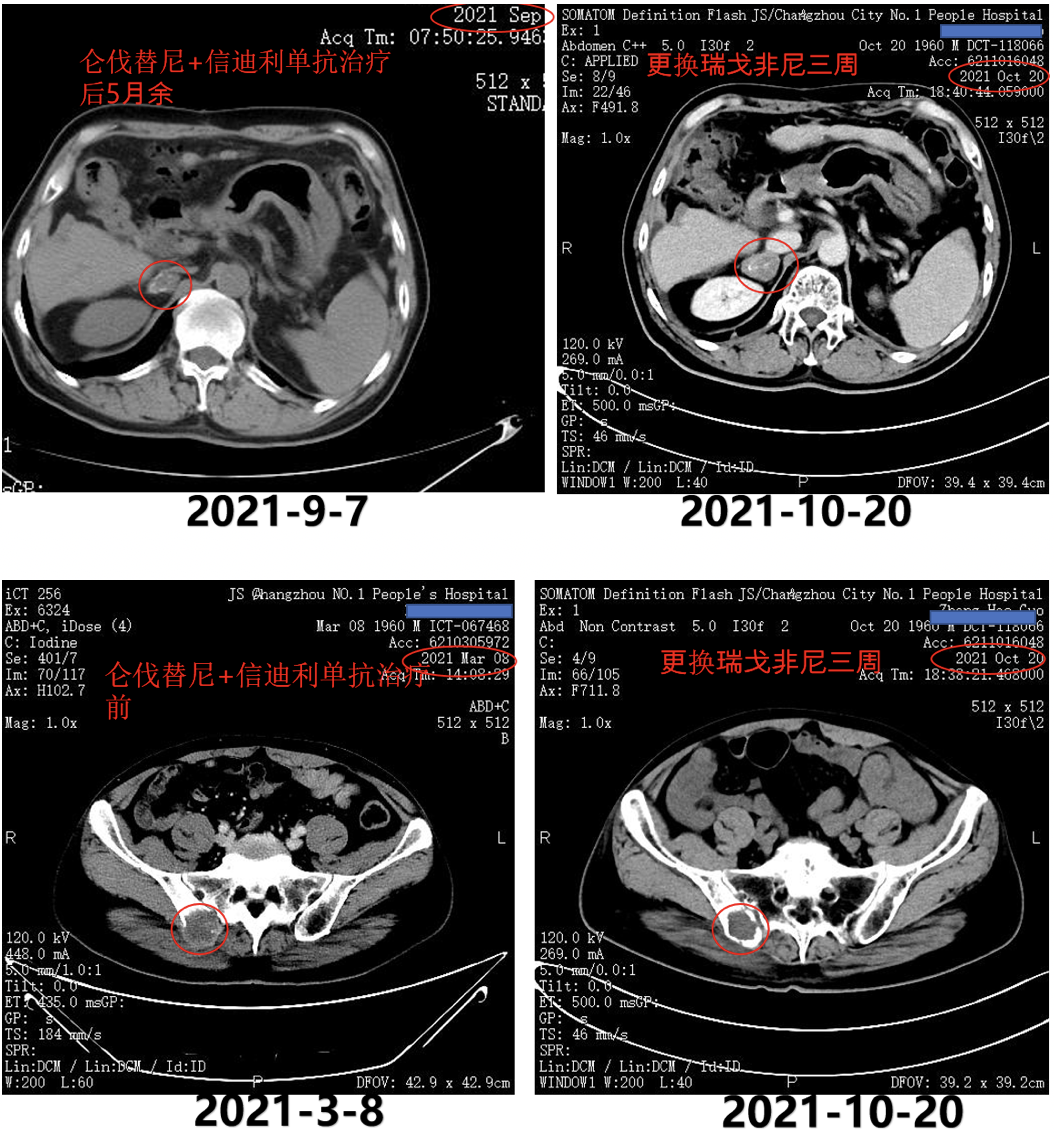

2021年4月29日、2021年6月11日、2021年7月2日、2021年8月16日和2021年9月6日复查AFP分别为242ng/ml、11.93ng/ml、16.62ng/ml、52.61ng/ml和142.1ng/ml。2021年9月7日复查CT示,肺部病灶基本消失,双侧肾上腺病灶明显缩小(图7)。

图7.2021年9月7日复查CT

二线治疗——瑞戈非尼联合信迪利单抗

2021年9月27日AFP为396ng/ml,疾病进展。2021年9月28日口服瑞戈非尼80mg,每天一次,口服三周,停一周;继续信迪利单抗200mg,三周方案治疗。

2021年10月18日AFP为443.9ng/ml。2021年10月20日复查CT示,肾上腺病灶较前明显增大,髂骨病灶缩小(图8)。

图8.2021年10月20日复查CT